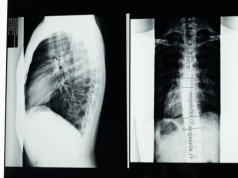

Rutynowe testy krwi wystarczą, by dowiedzieć się, jaka przyszłość czeka pacjenta z uszkodzeniem rdzenia kręgowego. Udowodnili to badacze z Uniwersytetu Waterloo i Uniwersytetu Kalifornijskiego. Dotychczasowe badania były drogie i bardzo zawodne. Szykuje się więc prawdziwy przełom.

Rdzeń kręgowy łączy nasz mózg z ciałem. Utrata tego połączenia oznacza niezdolność do chodzenia, siedzenia lub korzystania z toalety. Jednak naukowcy znaleźli sposób, aby organizm mógł zregenerować się samodzielnie.

Urazy rdzenia kręgowego należą do najbardziej wyniszczających schorzeń neurologicznych, prowadząc nie tylko do utraty kontroli nad mięśniami, lecz także do zaburzeń czucia i percepcji położenia ciała. Te dwa elementy – ruch i informacja sensoryczna –...